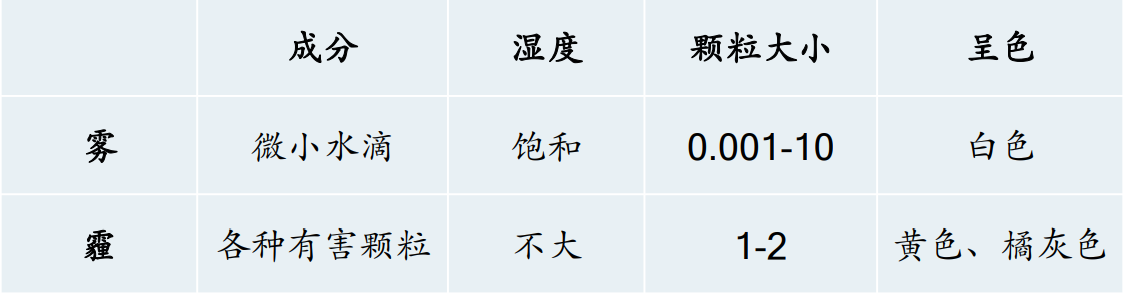

霾与雾 (Smog and Fog) 的对比

共同点:大气透明度降低,能见度差。

不同点(霾的特点)

PM(Particulate Matter)